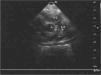

Se realizó ecocardiograma transtorácico: situs y concordancias adecuadas. Válvula pulmonar fina con buena movilidad y con regurgitación moderada. El tronco de la arteria pulmonar está dilatado con hipertensión pulmonar grave. Existe un defecto estructural en el septo aortopulmonar, antes de la división de las ramas pulmonares con comunicación anómala entre aorta ascendente y arteria pulmonar.